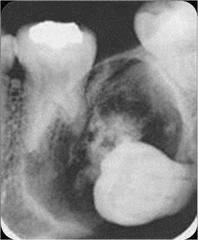

-obstruction in the gland hard nodule in soft tissue at a salivary gland -calcification of material -can be seen radiographically